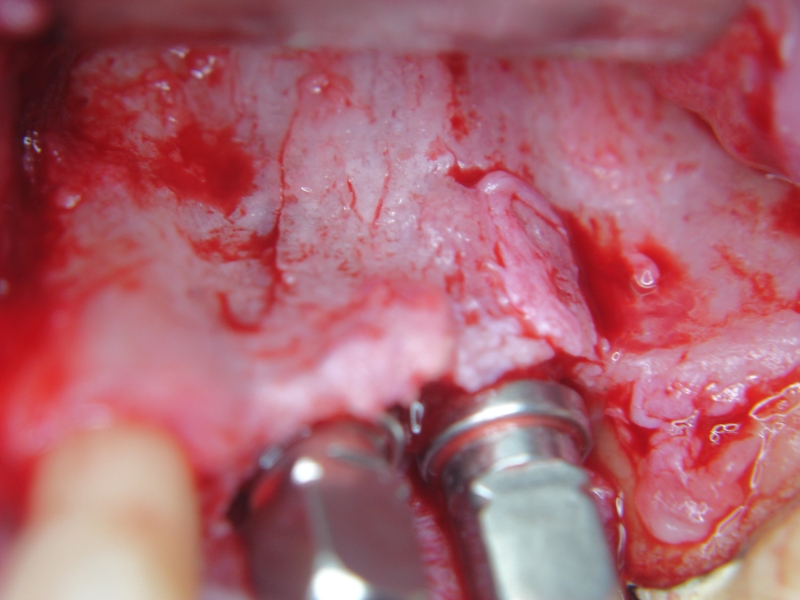

Three implants placed in a narrow posterior mandible